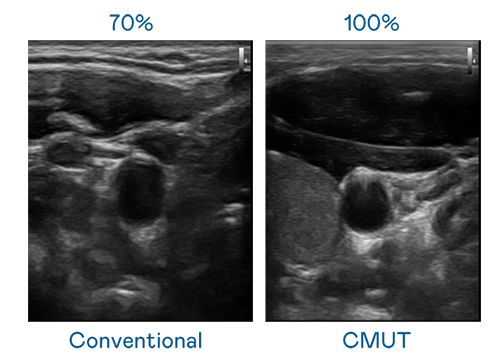

CMUT 技术是一种用电容式微机电元件来产生超音波讯号的技术。与传统 PZT 压电式技术相比,CMUT 频宽增加 30%,更宽频的超音波讯号让影像解析度大幅提升,是实现高影像品质医疗超音波扫描、促进精准医疗发展的关键技术。

超音波影像的解析度高低,首先取决于探头能发出的讯号频宽。z6mg·人生就是博 CMUT 可提供高清晰的超音波讯号,提供高频宽、高灵敏度、影像纹理细节更高的超音波影像,协助医护人员缩短影像判读时间及利用精准的医疗影像进行诊断。